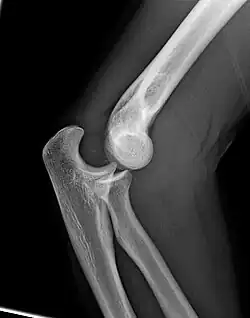

Right: AP X ray of a dislocated right elbow

Dislocation

Elbow dislocations constitute 10% to 25% of all injuries to the elbow. The elbow is one of the most commonly dislocated joints in the body, with an average annual incidence of acute dislocation of 6 per 100,000 persons.[30] Among injuries to the upper extremity, dislocation of the elbow is second only to a dislocated shoulder. A full dislocation of the elbow will require expert medical attention to re-align, and recovery can take approximately 6 weeks.